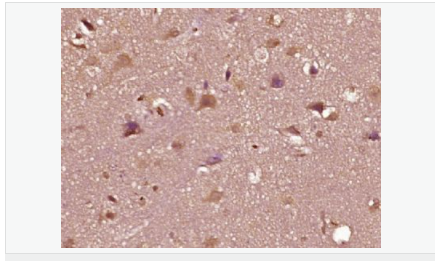

AR是一個由917個氨基酸組成的蛋白質,位于雄激素靶組織細胞中或細胞表面上的特異分子部位或結構。 AR在前列腺癌中起著重要的作用,研究表明AR的表達與組織分型形成一定的相關性 ,AR在高分化的腫瘤中表達較多,而在低分化的腫瘤中表達較少。用于前列腺癌的檢測,指導臨床治療,目前可用于乳腺癌、食道癌等各項腫瘤的研究。